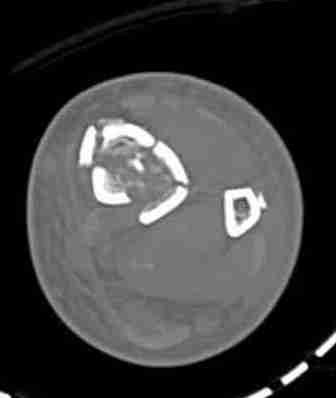

КТ пилона имеем.